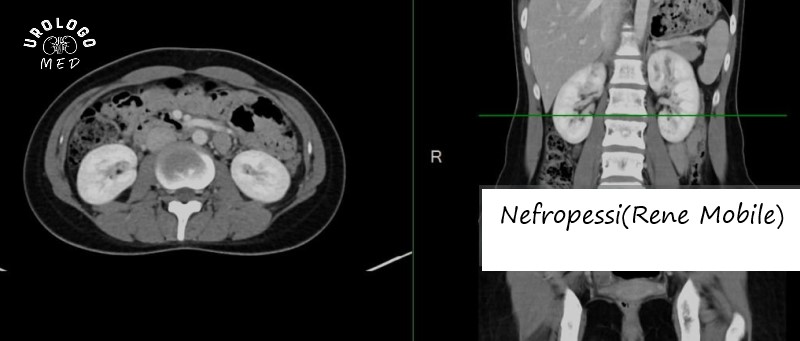

Nefropessi(Rene Mobile): Procedure, Recupero e Consigli

La ptosi renale, comunemente chiamata "rene mobile", rappresenta una condizione in cui il rene si sposta dalla sua posizione anatomica normale. Questo accade principalmente a causa dell'indebolimento dei tessuti di supporto e della riduzione del grasso che normalmente mantiene il rene nella sua sede. È un disturbo che colpisce prevalentemente le donne, con il rene destro più frequentemente interessato. La Nefropessi è l'intervento chirurgico risolutivo che consente di riposizionare e fissare stabilmente il rene nella sua sede naturale, prevenendo così ulteriori spostamenti e le complicazioni associate.